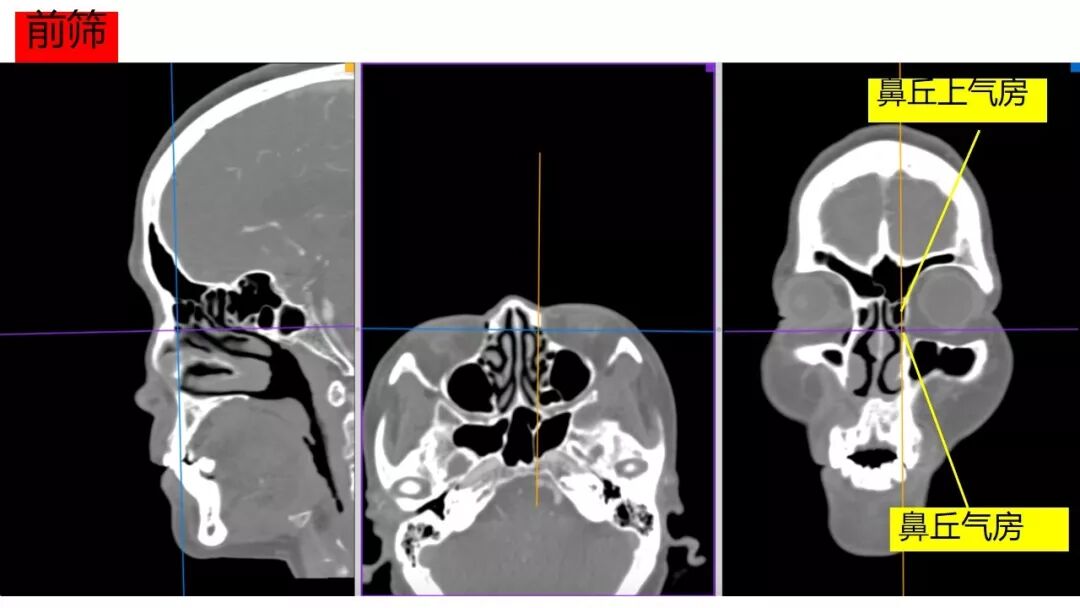

Osirix冠矢轴